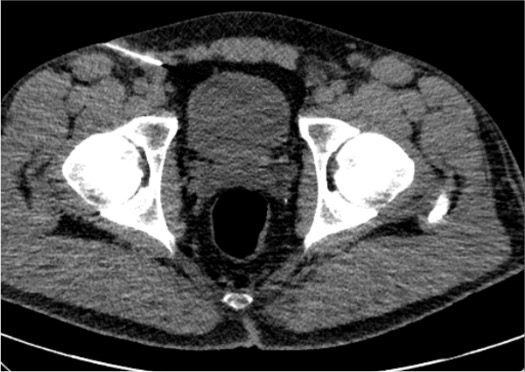

Obturator Nerve

- Arises from L2–L4; exits pelvis through obturator foramen

- Divides into anterior branch (hip adductors, medial thigh sensation) and posterior branch

- Target: CT-guided; obturator foramen or medial to femoral vessels

- Approach: CT supine; coronal plane most useful; 22G needle

- Motor risk: adductor weakness — counsel about driving

| Nerve | CT Target | Best CT Plane | Key Anatomy |

|---|---|---|---|

| Obturator | Obturator foramen; medial to femoral vessels | Coronal (most useful) | Anterior / posterior division at foramen |